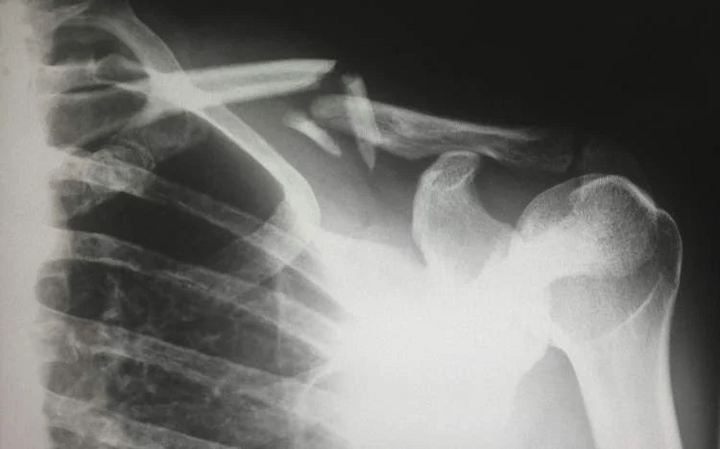

Các bác sĩ tại Bệnh viện Y học cổ truyền XinDu, Thành Đô, Trung Quốc vừa báo cáo về trường hợp bất thường của một bệnh nhân tại địa phương. Người phụ nữ giấu tên, 48 tuổi bị gãy xương chỉ vì nằm lăn lộn trên giường.

Theo Tiến sĩ Long Shuang, các xét nghiệm được thực hiện tại bệnh viện cho thấy nồng độ vitamin D trong cơ thể của người phụ nữ cực kỳ thấp. Điều này đẩy nhanh quá trình yếu xương và gây ra chứng loãng xương nghiêm trọng.

Ở người trung niên, việc thiếu hụt vitamin D kéo dài có thể gây ra loãng xương, dẫn đến đau xương và yếu cơ. Tình trạng này dẫn đến quá trình khoáng hóa xương, khiến xương bị suy yến, mềm, dễ biến dạng và gãy hơn.